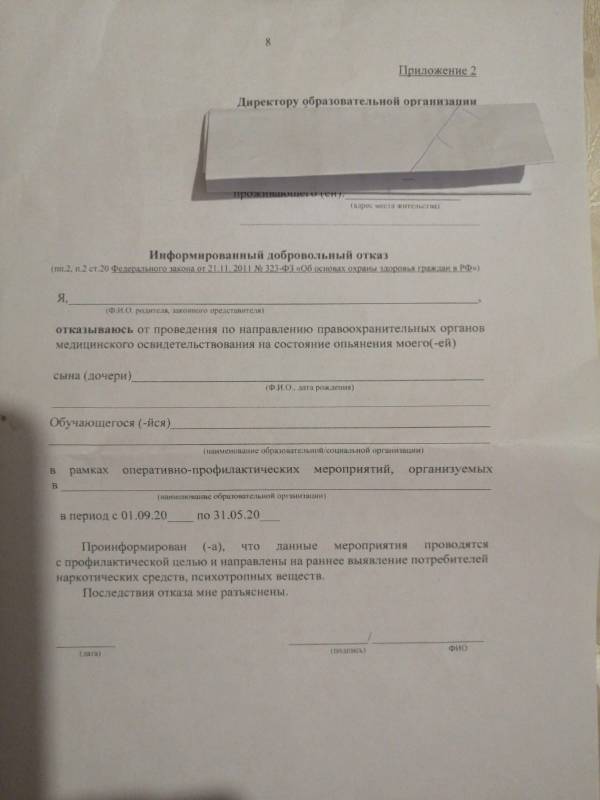

Какое отношение все вышеперечисленное имеет к обычным школьникам? Получается, что в данном случае сотрудники правоохранительных органов должны выписать направление на мед. освидетельствование в отношении несовершеннолетнего по основанию, которое звучит как «на всякий случай» или «просто так», или «почему бы и нет». Это неправовые, абсурдные основания, однако неравнодушные, активные родители прислали нам фото бланка для отказа от подобных мероприятий с разъяснением неких последствий

Такой документ, в силу его правовой неопределенности, мы подписывать не рекомендуем. Для мотивированного и твердого отстаивания своей позиции, мы рекомендуем подать письменный отказ, приведенный на законных основаниях, чтобы избежать риска нелепых претензий и обезопасить своего ребенка от сомнительного мед. вмешательства:

- СКАЧАТЬ отказ от мед. освидетельствования на выявление алко/нарко опьянения